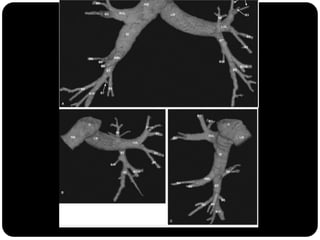

Traquéia       Brônquios principais originam-se da traquéia

Brônquios –     na carina;

PRINCIPAIS

Bronquíolos    Brônquio direito: ângulo mais obtuso com o

Alvéolos        eixo longo da traquéia;

 Direito(2,2cm) mais curto que o

esquerdo(5cm);

Traquéia      BPD:   BLSD

Brônquios –

BI - BLM

LOBARES              BI – BLID

Bronquíolos

Alvéolos

BPE:   BLSE

BLIE